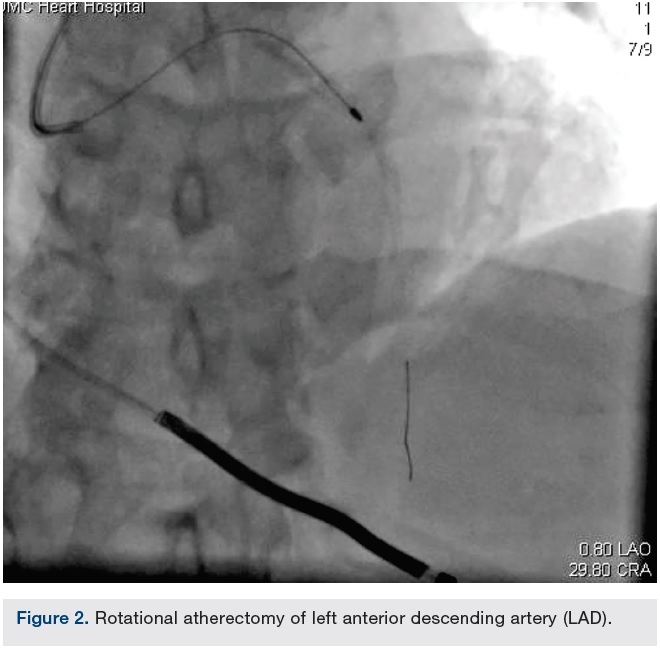

A 69-year-old male with coronary artery disease, prior left anterior descending artery (LAD) stenting, ischemic cardiomyopathy, hypertension, diabetes, and hyperlipidemia underwent coronary angiography for worsening angina and anterior ischemia on stress testing. Coronary vessels were heavily calcified. A prior stent was visualized in the proximal and mid LAD with 50% in-stent stenosis proximally and 95% sub-total occlusion just distal to the stent or within the stent (difficult to delineate due to severe calcification). The LAD lesion was thought to be the culprit. Rotational atherectomy was undertaken due to the calcification distal to the stent.

A 6 French Ultimate 2 guide (Merit Medical) through a right radial approach was used to engage the left main. A Balance Middleweight (BMW) wire (Abbott Vascular) was passed distal to the LAD, then exchanged for an Extra Support RotaWire (Boston Scientific) via a Micro 14 catheter (Roxwood Medical). A 1.5 mm RotaLink Plus (Boston Scientific) was used for atherectomy and 2 runs were performed with no deceleration as per staff. The Rota burr popped through the lesion, then stalled.